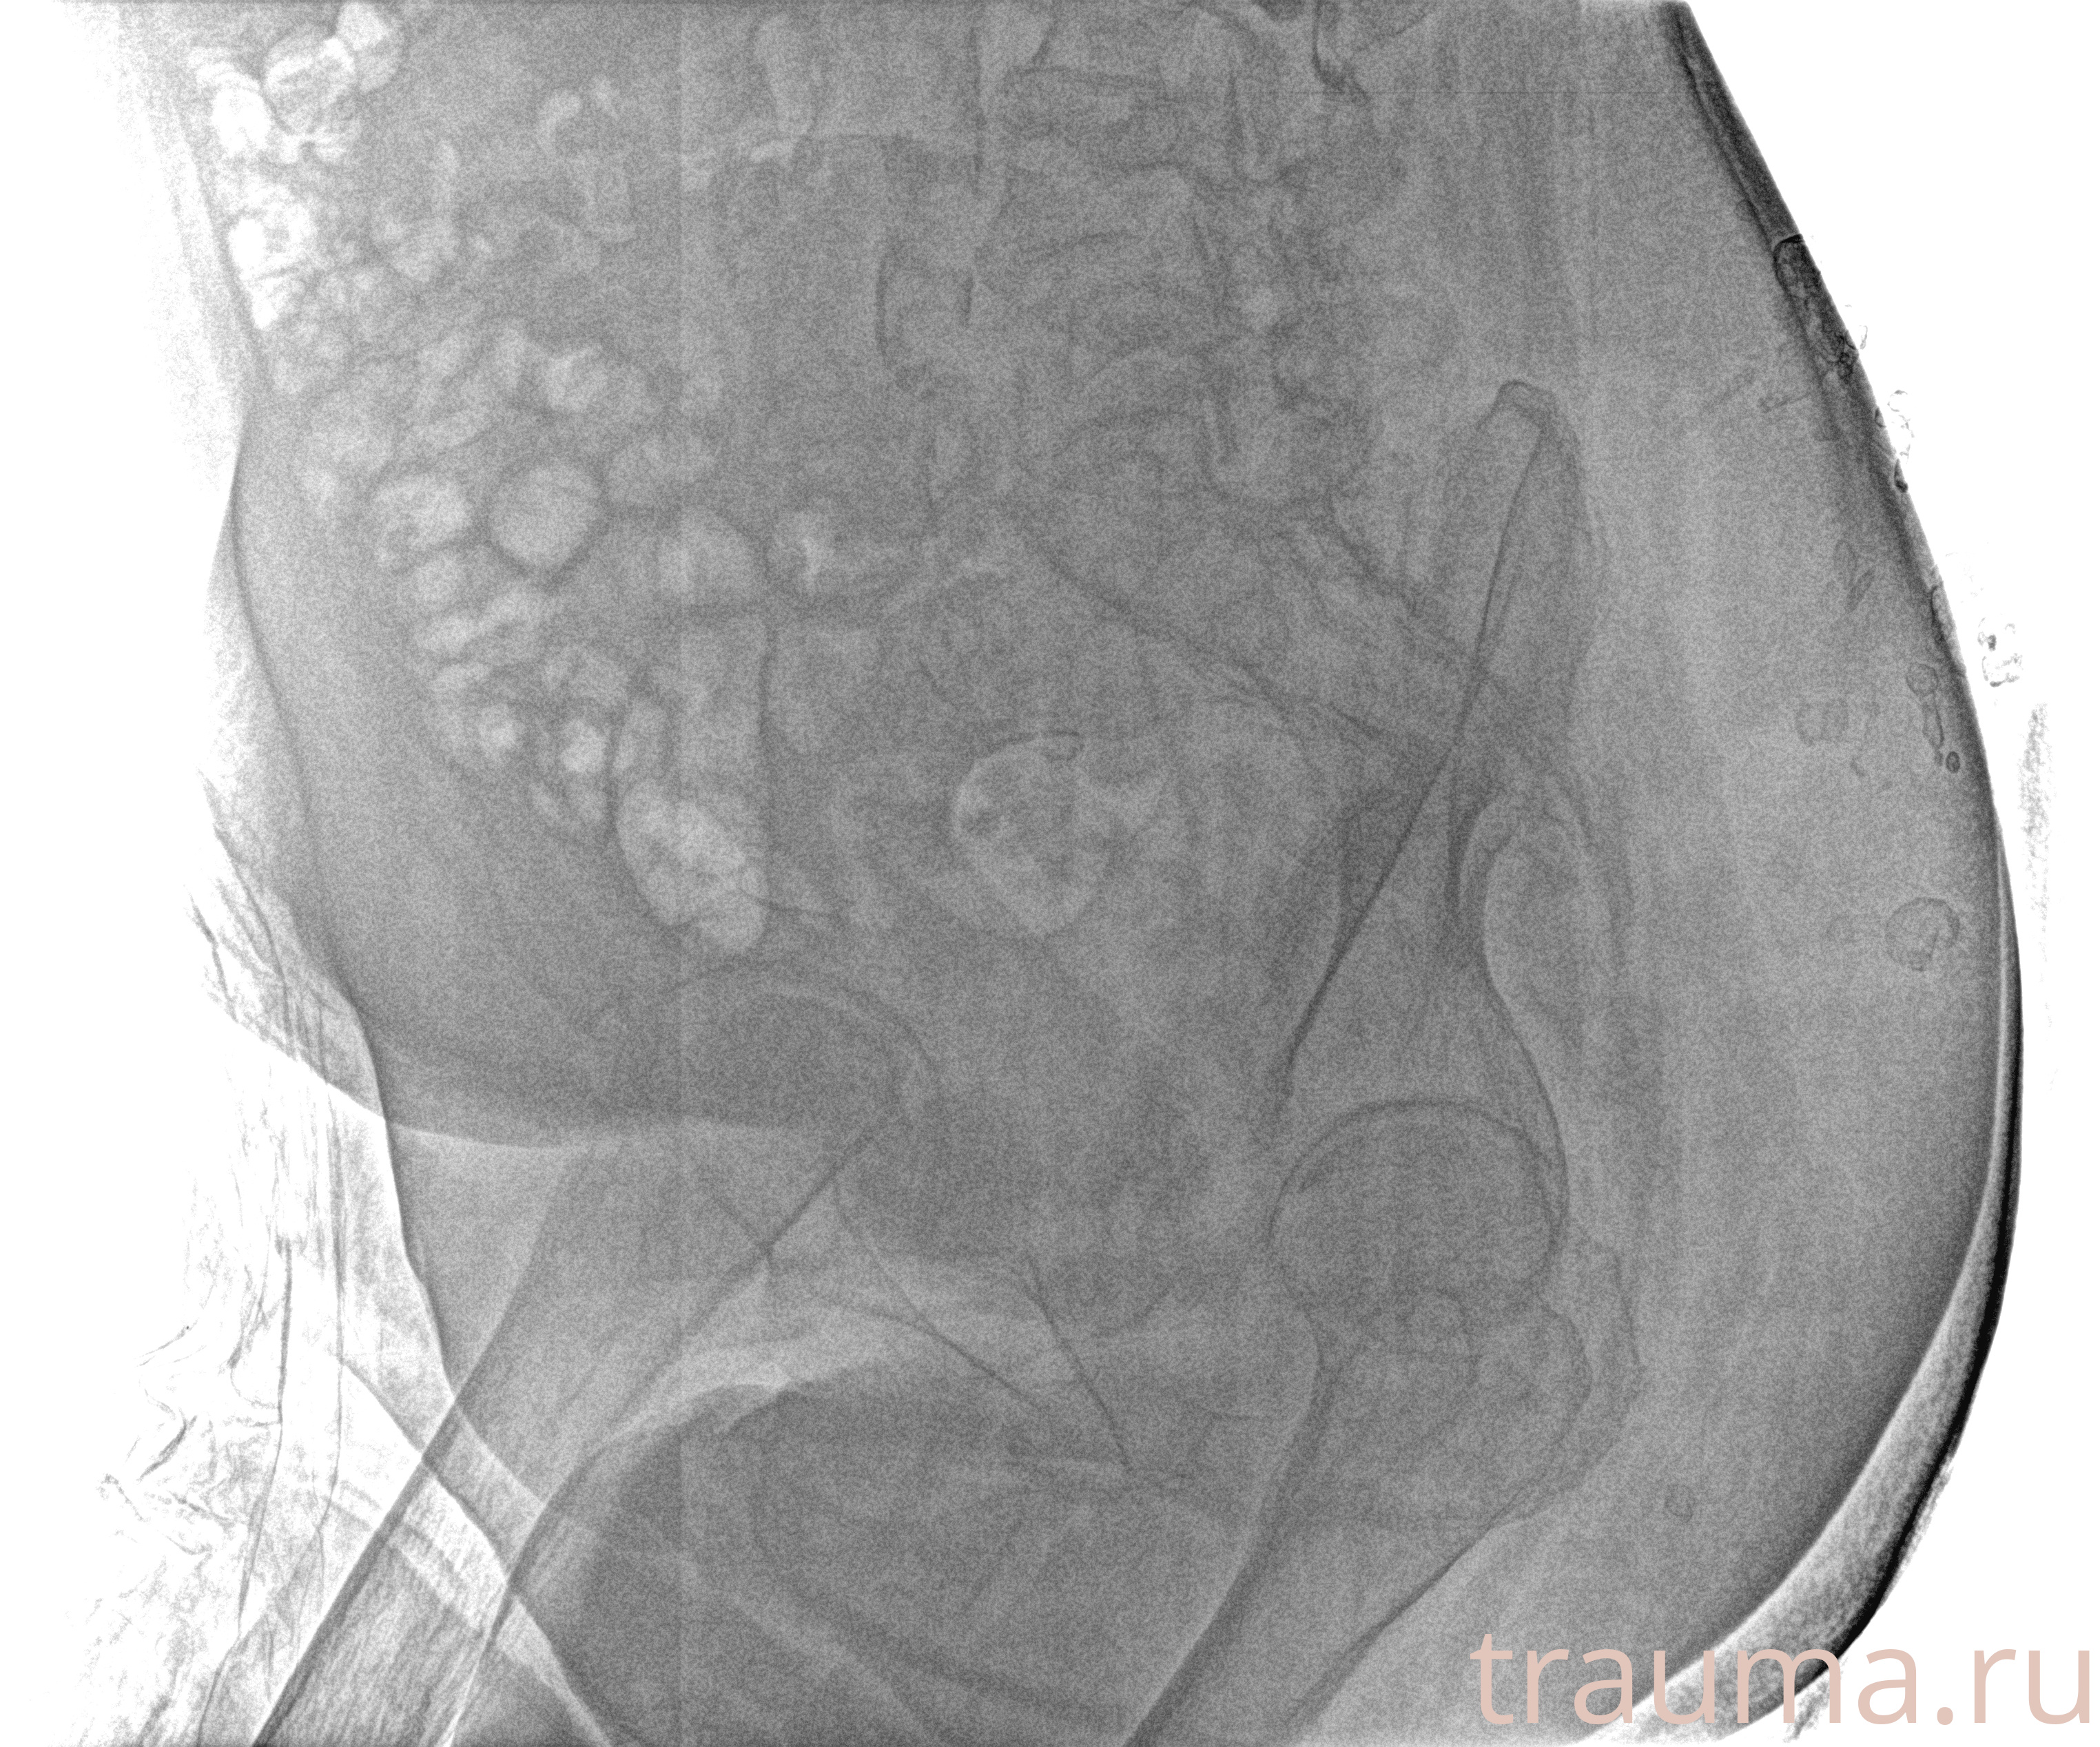

Рентген на дому: по вашему адресу приезжает врач-рентгенолог, травматолог-ортопед с мобильным рентгеновским аппаратом, проводит диагностику травмы или заболевания, делает необходимые рентгенограммы, дает рекомендации по дальнейшему лечению. Получить качественные снимки в домашних условиях возможно благодаря уникальной методике, разработанной МосРентген Центром для института  Склифосовского